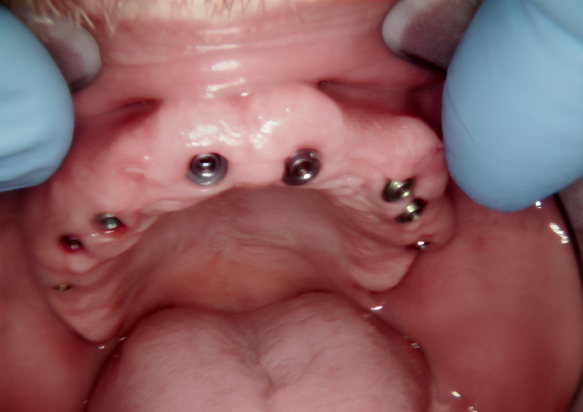

The implants were placed immediately following tooth extraction. They were positioned subcrestally — 2–3 mm below the bone crest — to allow for anticipated bone remodeling. A total of eight implants were placed in the maxilla and four in the mandible.

Placing the implants into the fresh extraction sockets allowed for optimal positioning for the future prosthetic restoration. The extractions were performed using the root shield technique, which is aimed at maintaining the thickness and height of the buccal and palatal bone walls. This technique, traditionally used for “conservation” even in case of delayed implantation, helps to minimize resorption and preserve the natural morphology of the alveolar ridge.